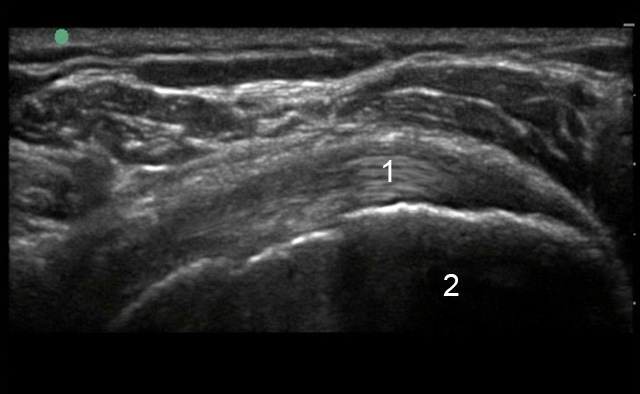

Shoulder Left Infraspinatus Longitudinal Image

Infraspinatus Tendon (IT)

Greater Tuberosity (GT)